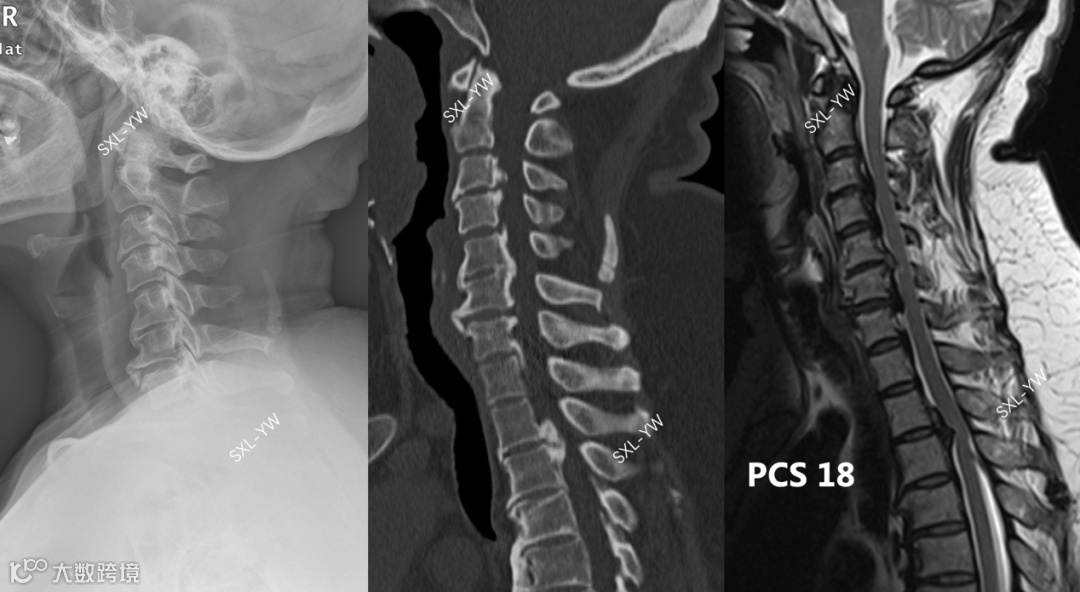

图10 该OPLL患者骨化累及上胸椎,超出K线使用范畴,手术减压范围超过C2-7节段,不能用K线做术前指导。该患者PCS评分高达18分,单开门术后神经功能改善的可能性很大

图11 参考PCS评分,上述患者接受了C3-T3的单开门手术,术后脊髓获得充分漂移